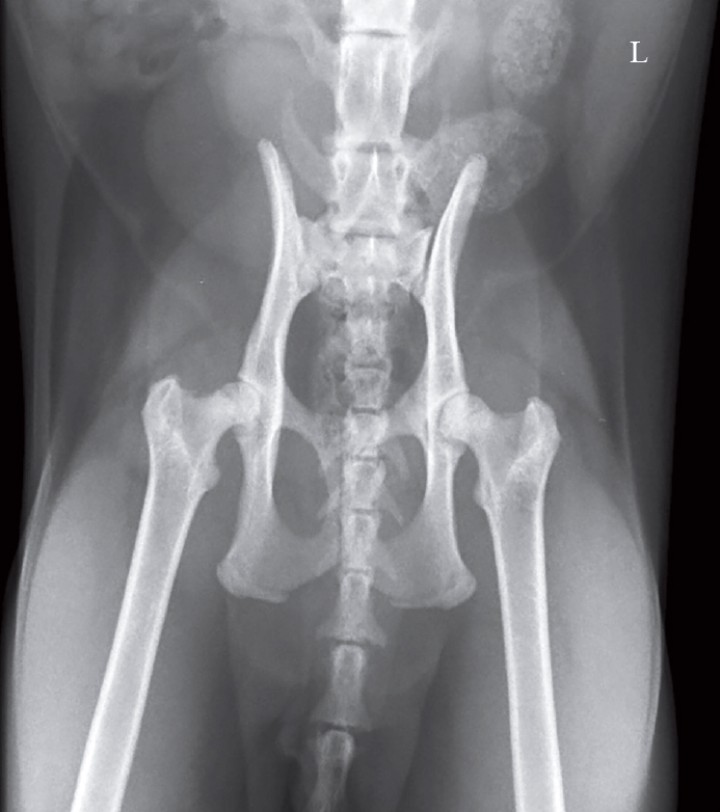

Se realizó una radiografía ventrodorsal de la cadera con los miembros en extensión (Fig. 1).

<p>Proyección ventrodorsal con los miembros en extensión de un gato Siamés, de 6 kg de peso y dos años de edad, macho, castrado que se presenta con un cuadro de debilidad de las extremidades posteriores y reacio a saltar desde hacía unas semanas.</p>

Figura 1

Proyección ventrodorsal con los miembros en extensión de un gato Siamés, de 6 kg de peso y dos años de edad, macho, castrado que se presenta con un cuadro de debilidad de las extremidades posteriores y reacio a saltar desde hacía unas semanas.